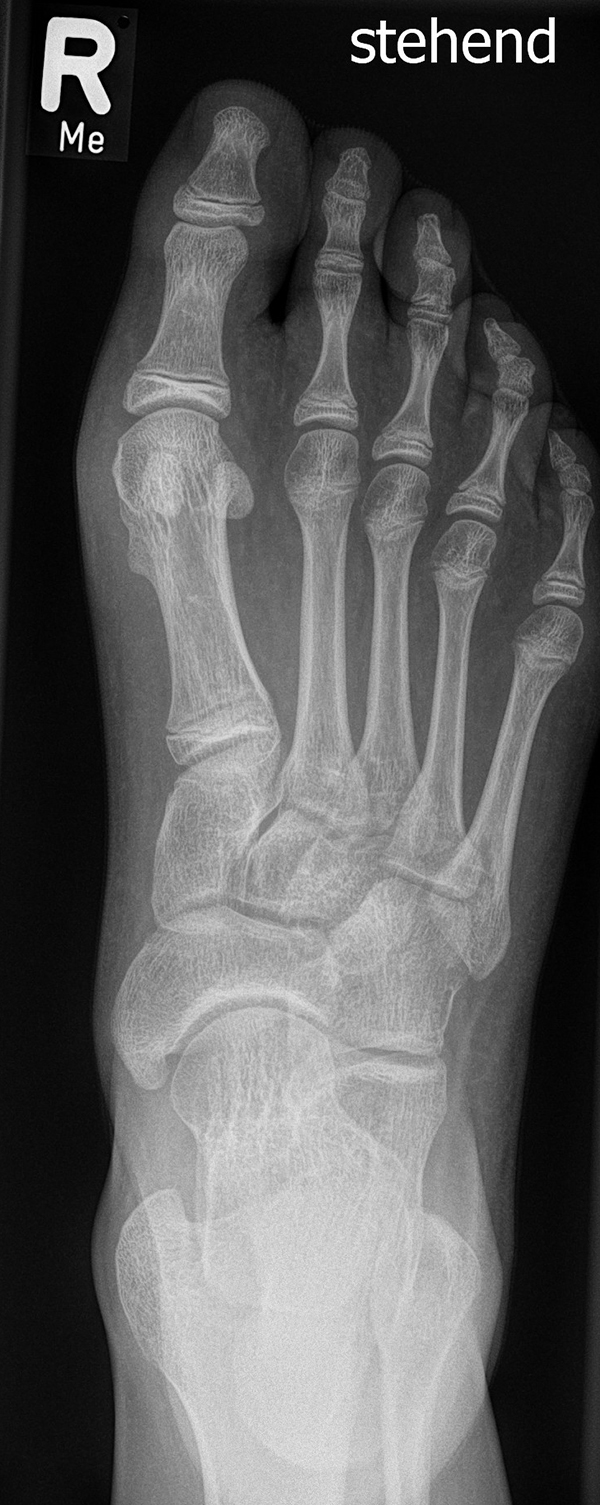

Damit die minimalinvasive Fußchirurgie zur Korrektur kindlicher oder jugendlicher Fußdeformitäten erfolgreich angewendet werden kann, erfordert die präoperative Diagnostik Röntgenbilder in drei Ebenen am stehenden Fuß. Röntgenbilder ohne Belastung des Fußes sind nicht zielführend. Im Fall von schweren Rückfußdeformitäten wird das obere Sprunggelenk in die radiologische Diagnostik mit einbezogen in Kombination mit der Rückfußaufnahme unter Belastung („Saltzman View“). Das OSG wird in zwei Ebenen geröntgt. Die streng seitliche Aufnahme des OSG kann bei den komplexen Fußdeformitäten mit der seitlichen Aufnahme des Fußes unter Belastung kombiniert werden. Das reduziert die diagnostische Strahlenbelastung der Kinder.

Indikationen für die beschriebenen Röntgenaufnahmen sind Klumpfußdeformitäten zur Beurteilung eines „flat top talus“ oder neurologische Grunderkrankungen mit varischer Fersenstellung wie zum Beispiel bei HSMN (Hereditäre Sensorische Motorische Neuropathie).